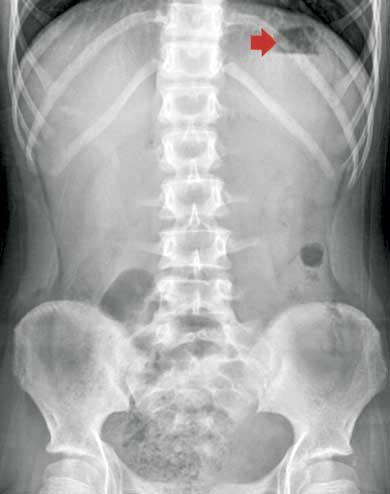

Fue hospitalizada en el servicio de Pediatría, donde se realizaron los siguientes estudios. Perfil inmunológico: factor reumatoide 2.67 UI/mL, velocidad de sedimentación globular 12 mm/h, anticuerpos anti-DNA doble cadena con resultado negativo, anticuerpos antinucleares negativos, complemento C3 93.6 mg/dL, complemento C4 29.9 mg/dL. Perfil infeccioso: anticuerpos IgG e IgM citomegalovirus negativos, anticuerpos IgG e IgM toxoplasma negativos. Radiografía de tórax simple: campos pleuropulmonares y ramas pulmonares normales, sin cardiomegalia o masas ocupativas (figura 1). Radiografía de abdomen simple: aire en cámara gástrica, de escasa cantidad en colon y recto; colon descendente y recto sigmoides con imágenes sugestivas de fecalitos (figura 2). Ultrasonido de hígado y vías biliares: páncreas en situación habitual, con bordes regulares bien delimitados, cabeza y cola dentro de los parámetros normales, cuerpo aumentado de tamaño, en forma de herradura, sin evidencia de líquido peripancreático; hígado y vesícula biliar conservados (figura 3).